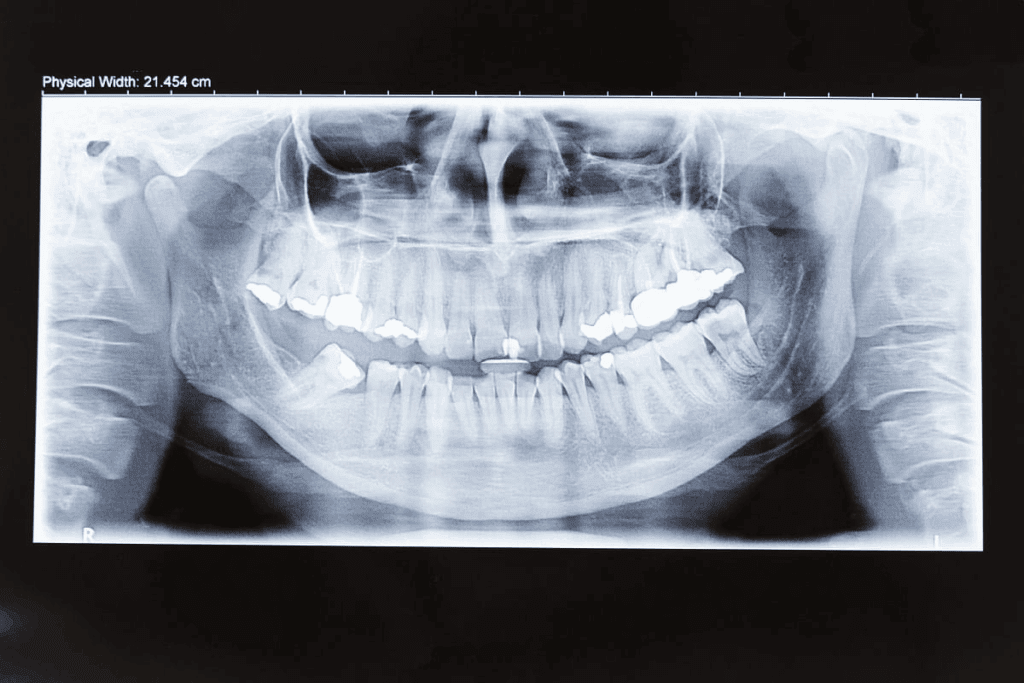

These X-rays are different from old dental X-rays. Old X-rays only show a small part of the mouth. But panoramic X-rays show the whole mouth, including teeth, jaws, and more.

Panoramic X-rays have big advantages over old X-rays. They let dentists see the whole mouth in one picture. This helps find problems that old X-rays miss, like hidden teeth or bone issues.

The Diagnostic Advantage of Full-Mouth Panoramic Views

Full-mouth panoramic views show your mouth’s structure clearly. They help us find issues that regular exams might miss.

- Identifying impacted teeth or developmental issues

- Finding bone loss or periodontal disease patterns

- Screening for cysts, tumors, or other pathologies

| Diagnostic Feature | Conventional X-Rays | Panoramic X-Rays |

|---|---|---|

| Coverage Area | Limited to specific areas | Full-mouth view |

| Radiation Exposure | Variable, often higher | Generally lower |

| Diagnostic Scope | Narrow focus | Broad overview |